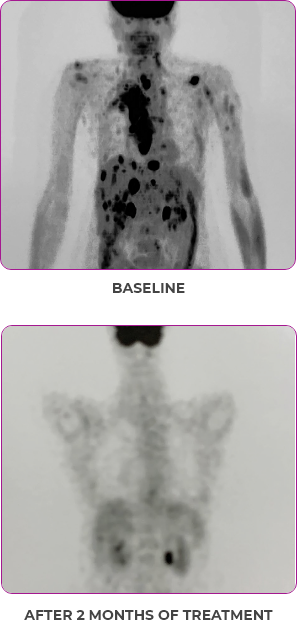

PATIENT CASE:

METASTATIC, RAIa-REFRACTORY,

PAPILLARY THYROID CANCER1

- 56-year-old female with PTCa that had metastasized to multiple sites, including the brain

- Progression after first- and second-line systemic treatment

- PRa after 4 weeks on VITRAKVI® (larotrectinib); CRa after 8 weeks

- At last assessment, complete response was sustained over an 11-month period

Clinical presentation1

- Patient was assessed to have metastatic, rapidly progressive, RAl-refractory PTC based on imaging that revealed multiple metastatic sites, including the neck, mediastinum, lung, scalp, and bones

- Biopsy of a scalp lesion helped to confirm the PTC metastasis

- Metastases to the brain and liver were observed after progression on systemic treatments

Response to VITRAKVI1

- After 8 weeks on VITRAKVI, all target lesions had disappeared, demonstrating a complete response

- The complete response was sustained over 11 months of treatment with VITRAKVI

- Patient experienced Grade 1 fatigue and mild hepatic enzyme elevation

Response in primary and metastatic lesions1

MRIa imagery of the lungs. Arrow indicates large target lesion in left lung.1

SCAN 1: LUNG

MRIa imagery of the brain. Arrow indicates large target lesion in left lung.1

aMRI, magnetic resonance imaging.

Images courtesy of Dr Fabian Pitoia.